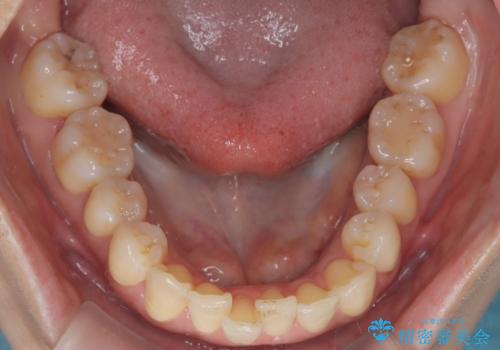

- 患者様は、上顎前歯の突出を改善したいとのご希望で来院されました。診断の結果、噛み合わせや全体的な歯列には大きな問題がないため、上顎のみを対象とした部分矯正が最適と判断しました。特に患者様は短期間での治療完了を希望されていたため、治療期間を約半年と設定しました。審美ワイヤーを用い、前歯を後方に移動させることで、自然で整った仕上がりを目指しました。治療計画は、患者様のスケジュールや希望を最大限考慮し、実現可能な目標を設定しました。